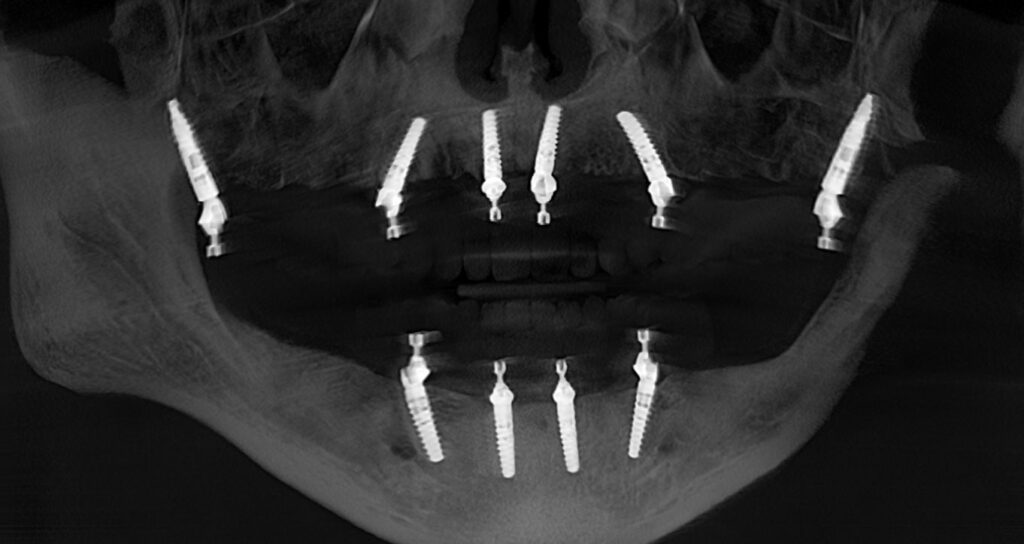

Implant Placement

Using precise, guided surgical protocols, implants are placed to create a strong, stable foundation for the full-arch restoration.